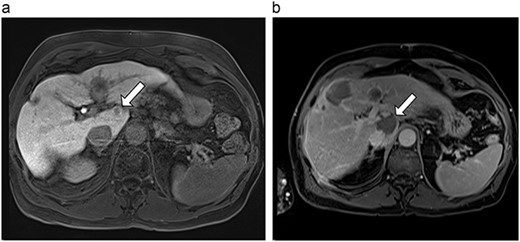

(a) Pre-ablation MRI demonstrating 5 mm lesion in caudate lobe of liver. (b) Post-ablation MRI (19 days postoperatively) demonstrating 36.2 mm complete ablation of caudate lesion.

| 3 (5a,b) | 68, F | Colon adenocarcinoma | 6 cycles modified FOLFOX-6 | 8 | Laparoscopic microwave ablation and low anterior resection of colon | 5 | 36.2 | 31.2 | 15 | No |